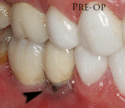

Fixture show

Recession of the gingiva leads to exposure of the metal abutment under a dental crown.

Black triangles

Black triangles caused by bone loss between implants and natural teeth